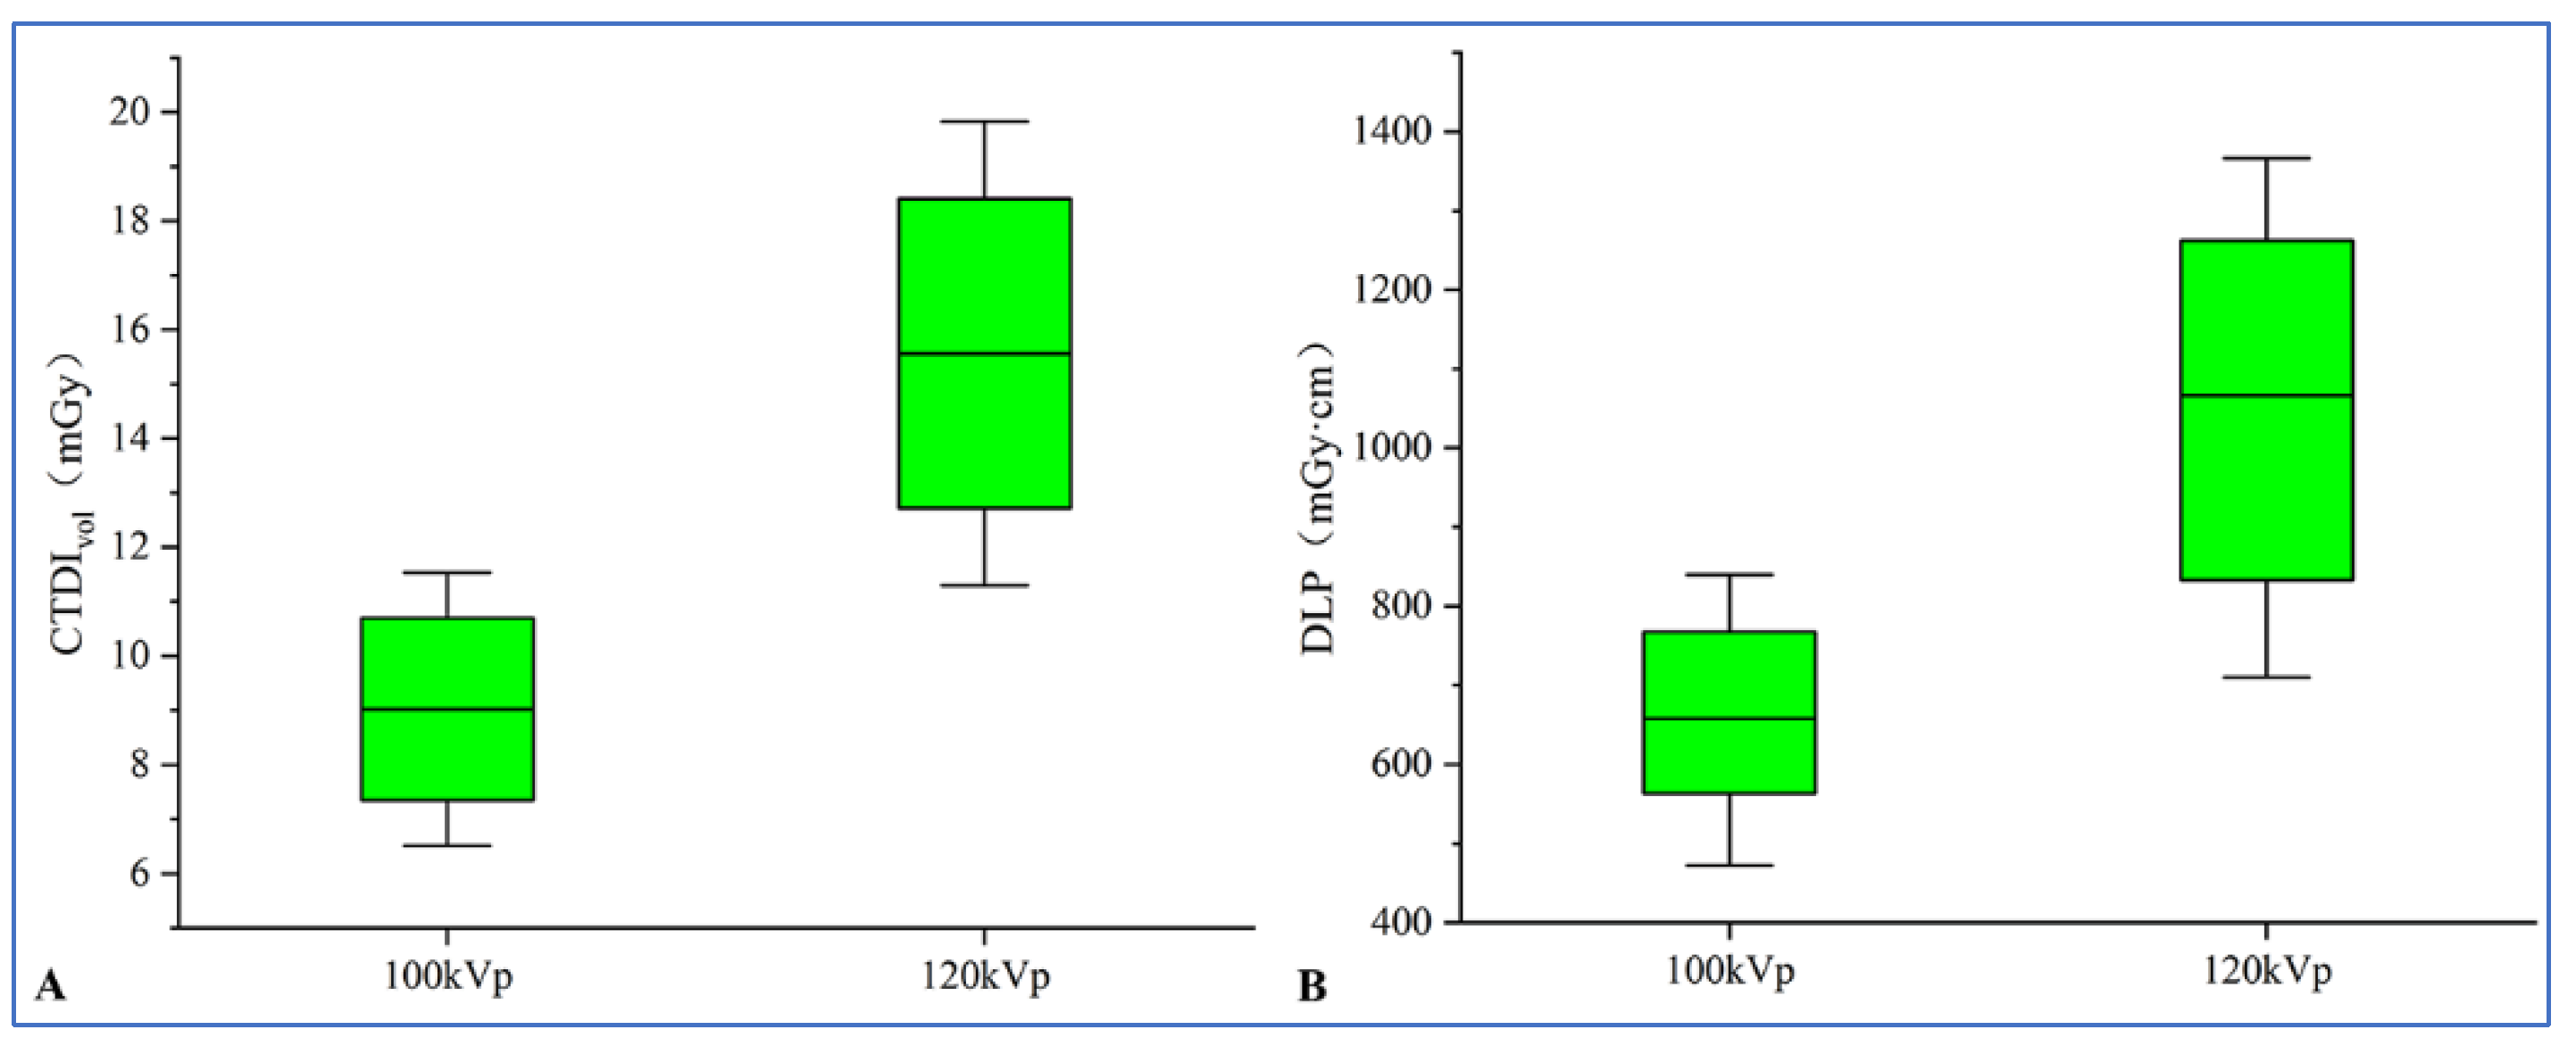

3.2. Objective Evaluation of Images